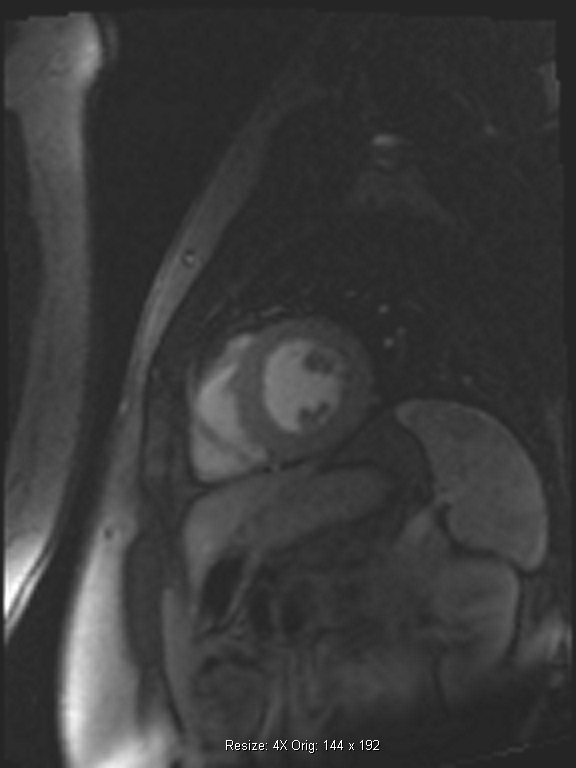

Τα βασικότερα πλεονεκτήματα της δυναμικής μαγνητικής τομογραφίας καρδιάς με αδενοσίνη (adenodine stress perfusion MRI) είναι η υψηλότερη ευαισθησία και ειδικότητα σε σχέση με τις υπόλοιπες διαγνωστικές μεθόδους δυναμικής απεικόνισης (σπινθηρογράφημα μυοκαρδίου, stress echo), η καταγραφή ακόμα και μικρών υπενδοκάρδιων ισχαιμικών περιοχών και μυοκαρδιακών ουλών, η καλύτερη διακριτική ικανότητα σε σχέση με το σπινθηρογράφημα του μυοκαρδίου και η ασφάλεια λόγω της απουσίας έκθεσης σε ιονίζουσα ακτινοβολία (εικόνες 1,2).

Εικόνα 1. Δυναμική μαγνητική τομογραφία καρδιάς με αδενοσίνη: